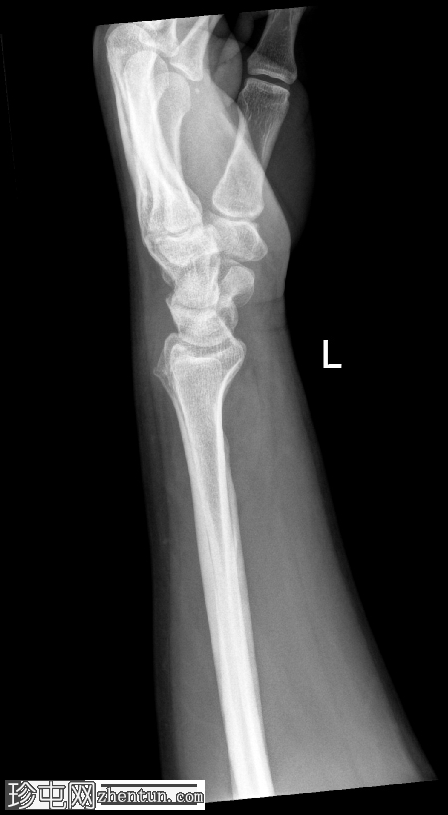

侧面

桡骨茎突骨折,符合Chauffeur骨折的诊断。骨折线斜向延伸至桡骨远端外侧,并累及桡骨茎突。

桡腕关节外观吻合;无明显关节面塌陷。舟骨和其他腕骨外观完整,腕骨列排列正常。尺骨远端和尺骨茎突完整。

旋前方肌脂肪垫抬高,与相关软组织肿胀和骨折相符。

本例中,桡骨茎突骨折块移位轻微,腕骨排列保持完整。可见旋前方肌脂肪垫隆起,提示与骨折下部相关的软组织水肿。